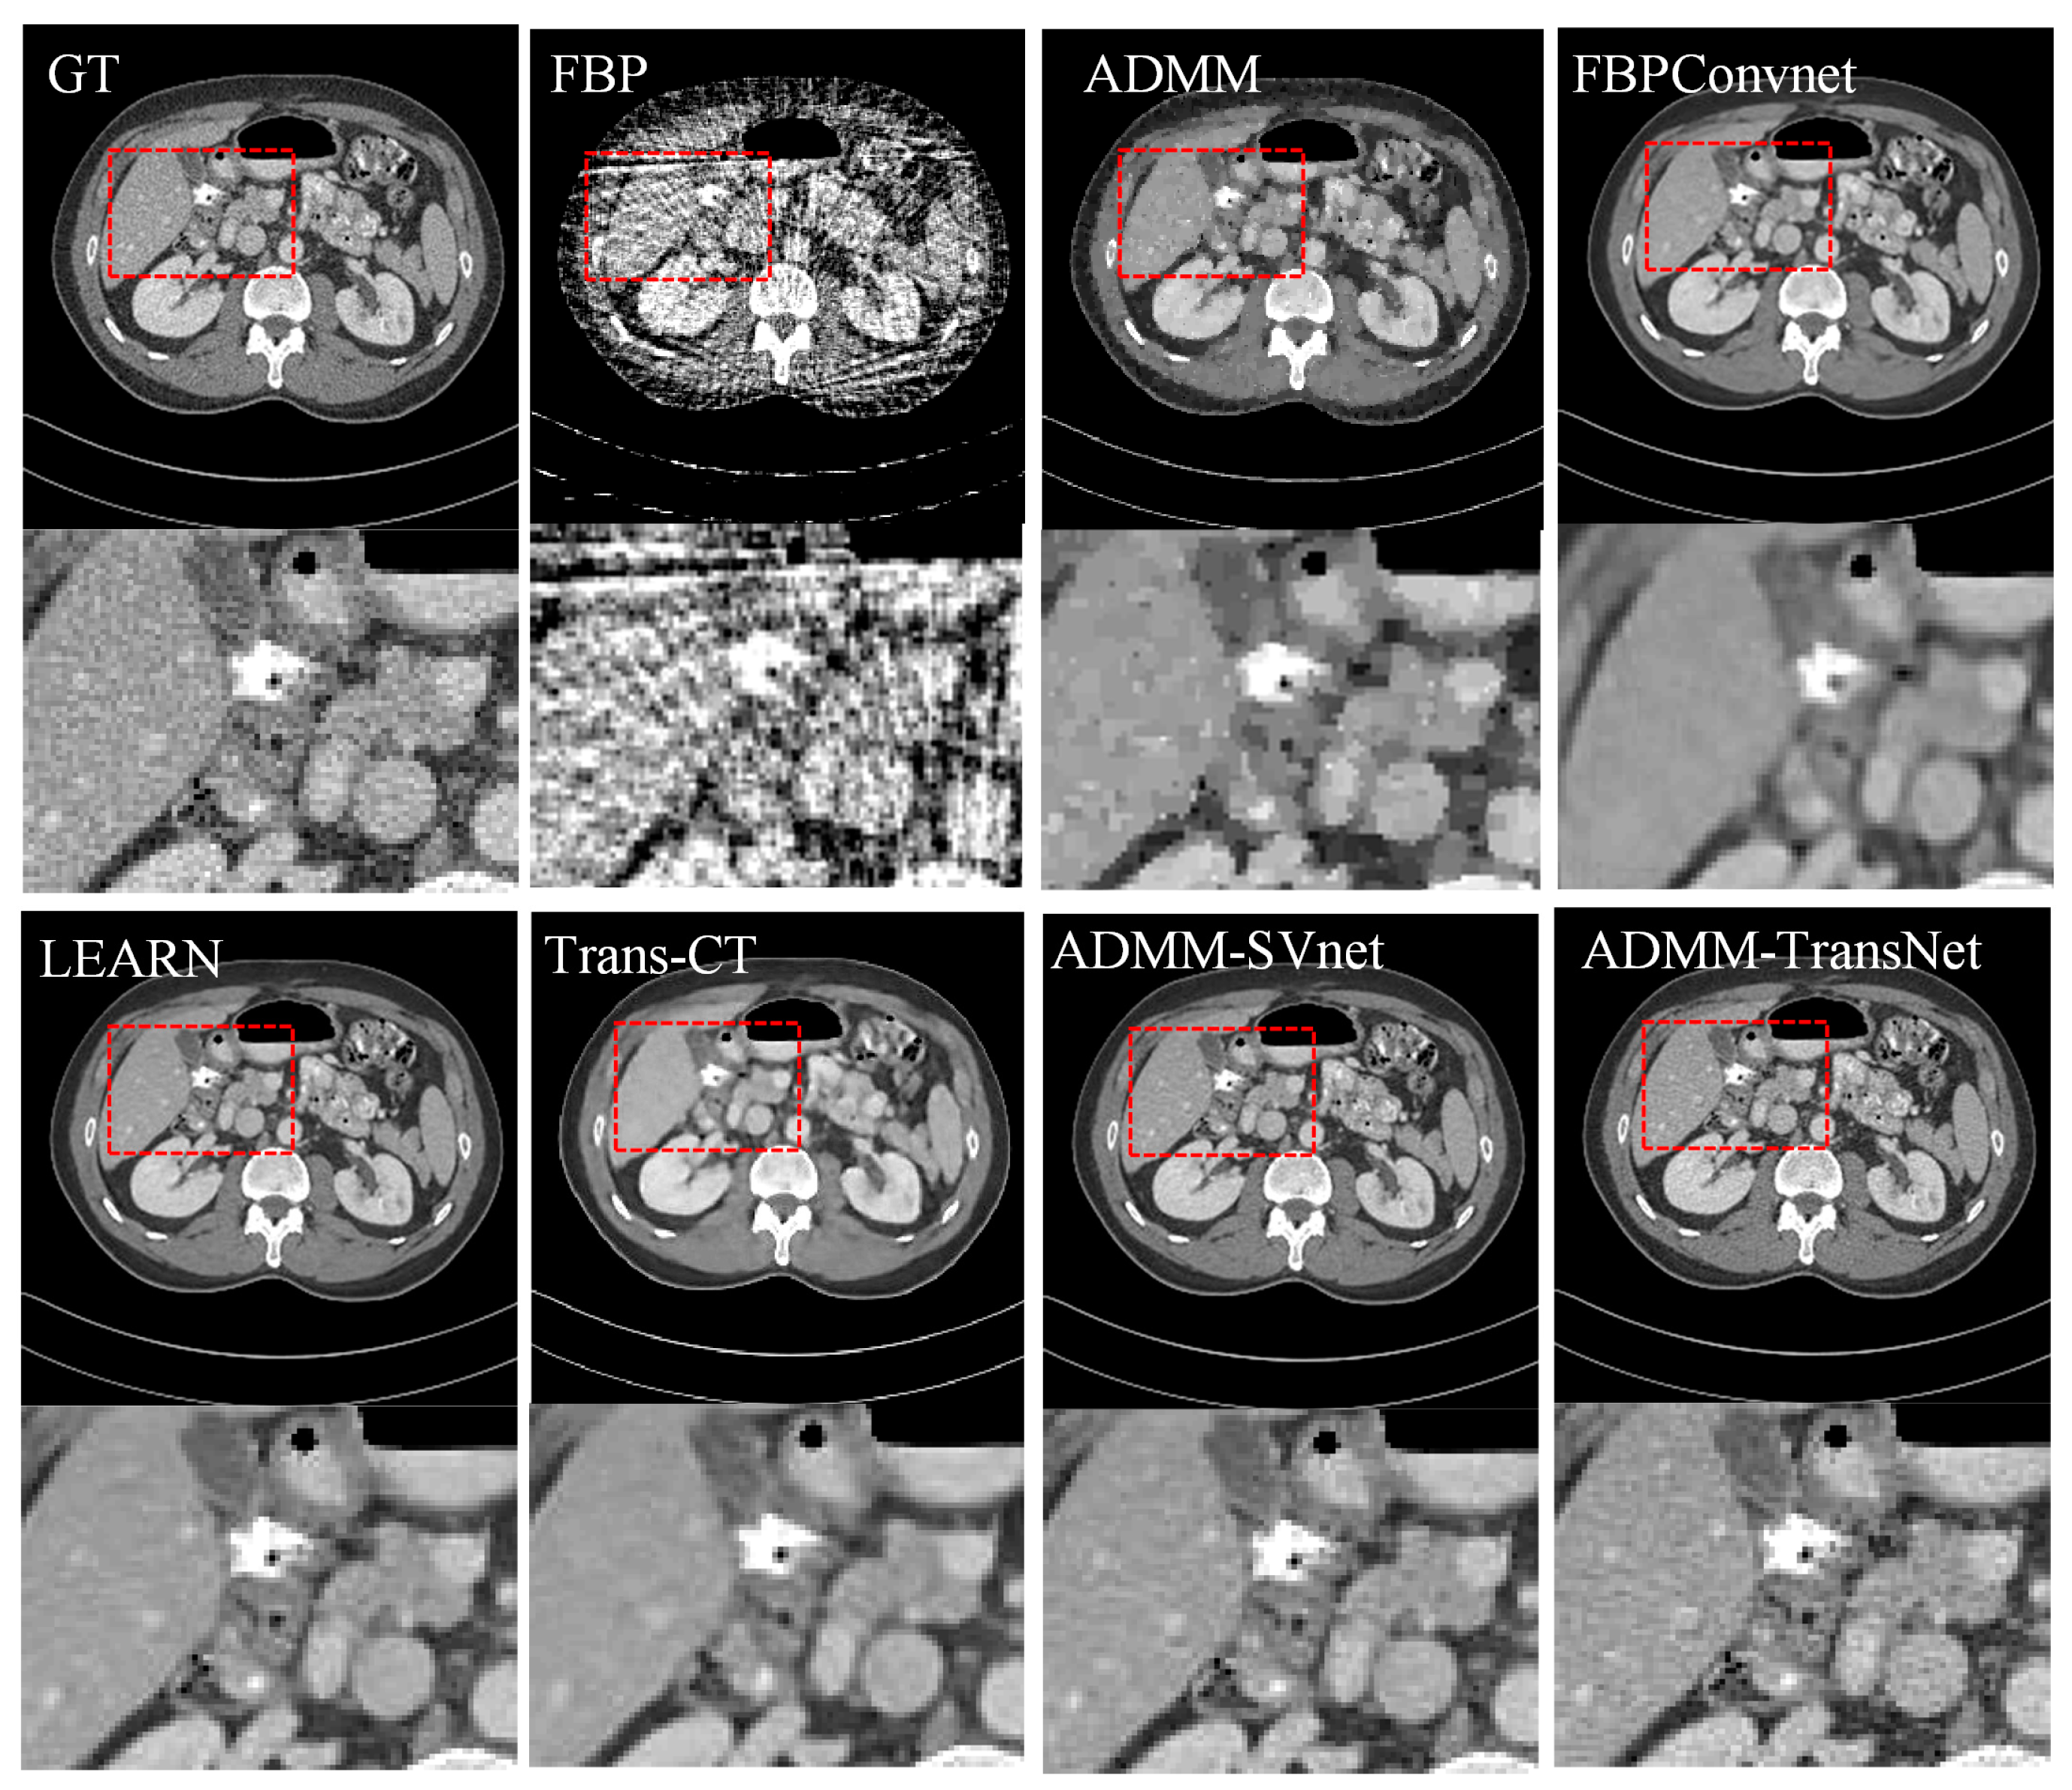

4.1. Simulation Data Research

| Views | 128 | 64 | 32 | ||||||

|---|---|---|---|---|---|---|---|---|---|

| Metric | PSNR | SSIM | MAE | PSNR | SSIM | MAE | PSNR | SSIM | MAE |

| FBP | 26.140 | 0.808 | 0.044 | 22.067 | 0.612 | 0.074 | 18.935 | 0.539 | 0.126 |

| ADMM | 33.751 | 0.929 | 0.021 | 30.883 | 0.915 | 0.027 | 29.753 | 0.907 | 0.038 |

| FBPConvNet | 39.854 | 0.952 | 0.020 | 34.243 | 0.938 | 0.028 | 30.648 | 0.916 | 0.035 |

| LEARN | 42.972 | 0.975 | 0.009 | 39.943 | 0.977 | 0.012 | 36.935 | 0.938 | 0.019 |

| Trans-CT | 40.877 | 0.966 | 0.011 | 35.855 | 0.941 | 0.019 | 32.430 | 0.922 | 0.023 |

| ADMM-SVnet | 43.229 | 0.995 | 0.007 | 42.974 | 0.989 | 0.008 | 40.212 | 0.972 | 0.013 |

| Ours | 44.633 | 0.996 | 0.006 | 43.726 | 0.992 | 0.007 | 42.036 | 0.979 | 0.011 |